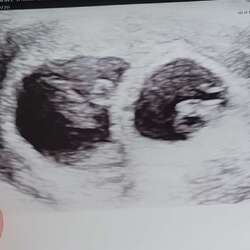

Ik had wel een buik, maar echt nog niet wat mensen 'verwachten' bij een tweeling. Kreeg commentaren als 'ben je wel zeker dat er een tweeling inzit'? Nu heb ik op 21-22 weken zo'n gekke krampen gekregen en is die buik er echt opeens uitgesprongen (alsin opeens x2). En nu op 24-25 weken is er weer zo'n gekke groei bezig. Alles op zijn tijd dus! :D